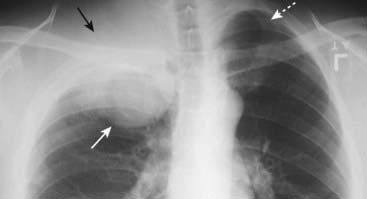

image

Figure 12-4 Mediastinal adenopathy from Hodgkin disease.

Lymphadenopathy frequently presents with a lobulated or polycyclic border due to the conglomeration of enlarged nodes that produce the mass (solid white arrows). This finding may help differentiate lymphadenopathy from other mediastinal masses. Mediastinal lymphadenopathy in Hodgkin disease is usually bilateral (dotted white arrows) and frequently asymmetric.

Figure 12-5 CT of anterior mediastinal adenopathy in Hodgkin disease.

On CT, lymphomas will produce multiple, lobulated soft-tissue masses or a large soft-tissue mass from lymph node aggregation (solid white arrows). The mass is usually homogeneous in density, as in this case, but may be heterogeneous when the nodes achieve a sufficient size to undergo necrosis (areas of low attenuation, i.e., blacker) or hemorrhage (areas of high attenuation, i.e., whiter). The superior vena cava (SVC) is compressed by the nodes while the ascending (A) and descending aorta (Ao) are typically less so.